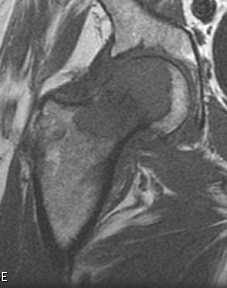

전이성 골종양의 경우 영상과 같이 치료가 무척 어렵습니다. 지푸라기라도 잡는 마음으로 방사선치료와 항암화학요법을 할 수 있습니다. 5년 생존율이 높아 보이는 환자군에서 장관골과 골반골의 임박 골절, 병적 골절 에는 예방적 고정술을 해볼 수 있습니다. (RT에도 효과가 없고, 2.5cm 정도로 큰 사이즈와 cortex가 50%이상 파괴되어 부러지기 직전일때, 소전자의 견열골절이 있을때 = Mirel 8점이상)